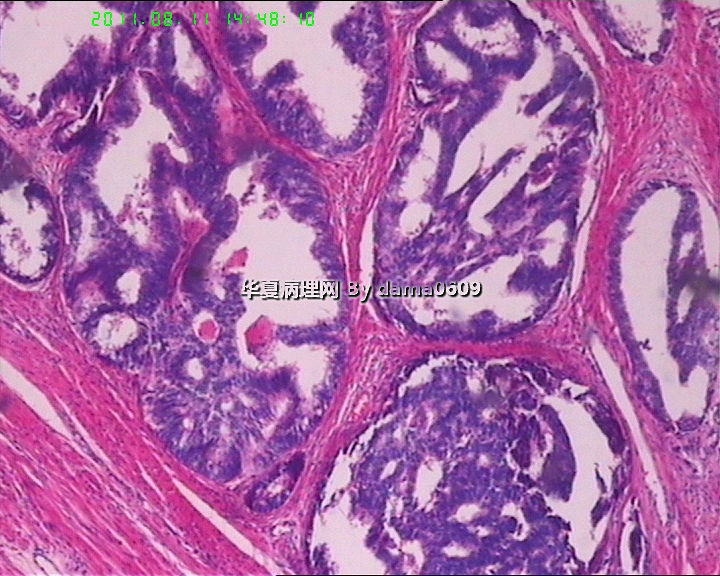

前列腺增生症标本内见有此病灶,请大家看看!!

图1